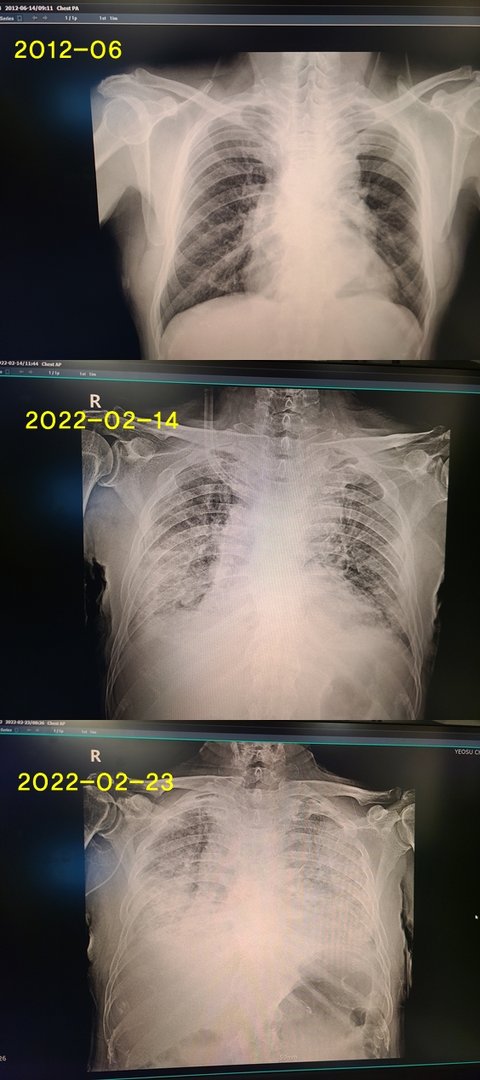

저희 아버지가 폐기종 및 폐렴으로 2/14일 지방 소도시 종합병원 입원항생제 3차까지 변경 후 투여 했으나상태 악화로 3차 병원 진료 시급 진단,(아직은 인공호흡기 미 시행 상태, 곧 해야 될 상황)그러나........

현재 HFNC Fio2 80%,  Flow 60L/min 중CRP 32.89 > 7.01 > 16.39  악화중Meropenem, Telcoplain q12hr, 3회, qd중